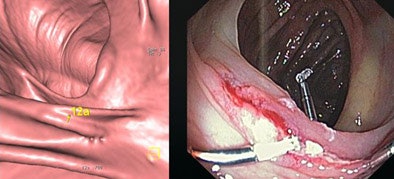

![]() |

| CAD and radiologist's marks concur for detection of a medium-sized polyp. |

Still, CAD missed two large polyps, including a malignancy. Pointing to the CT image of the mass, Graser noted its "large ridge-like structures, more like folds than caplike bulbous polyps. Maybe that was the reason CAD missed the lesion, which was easily detected by the radiologists. It was a transmural lesion. You see the lymph nodes up here -- definitely something you would not miss." CAD also missed a large adenoma that was harder to see.